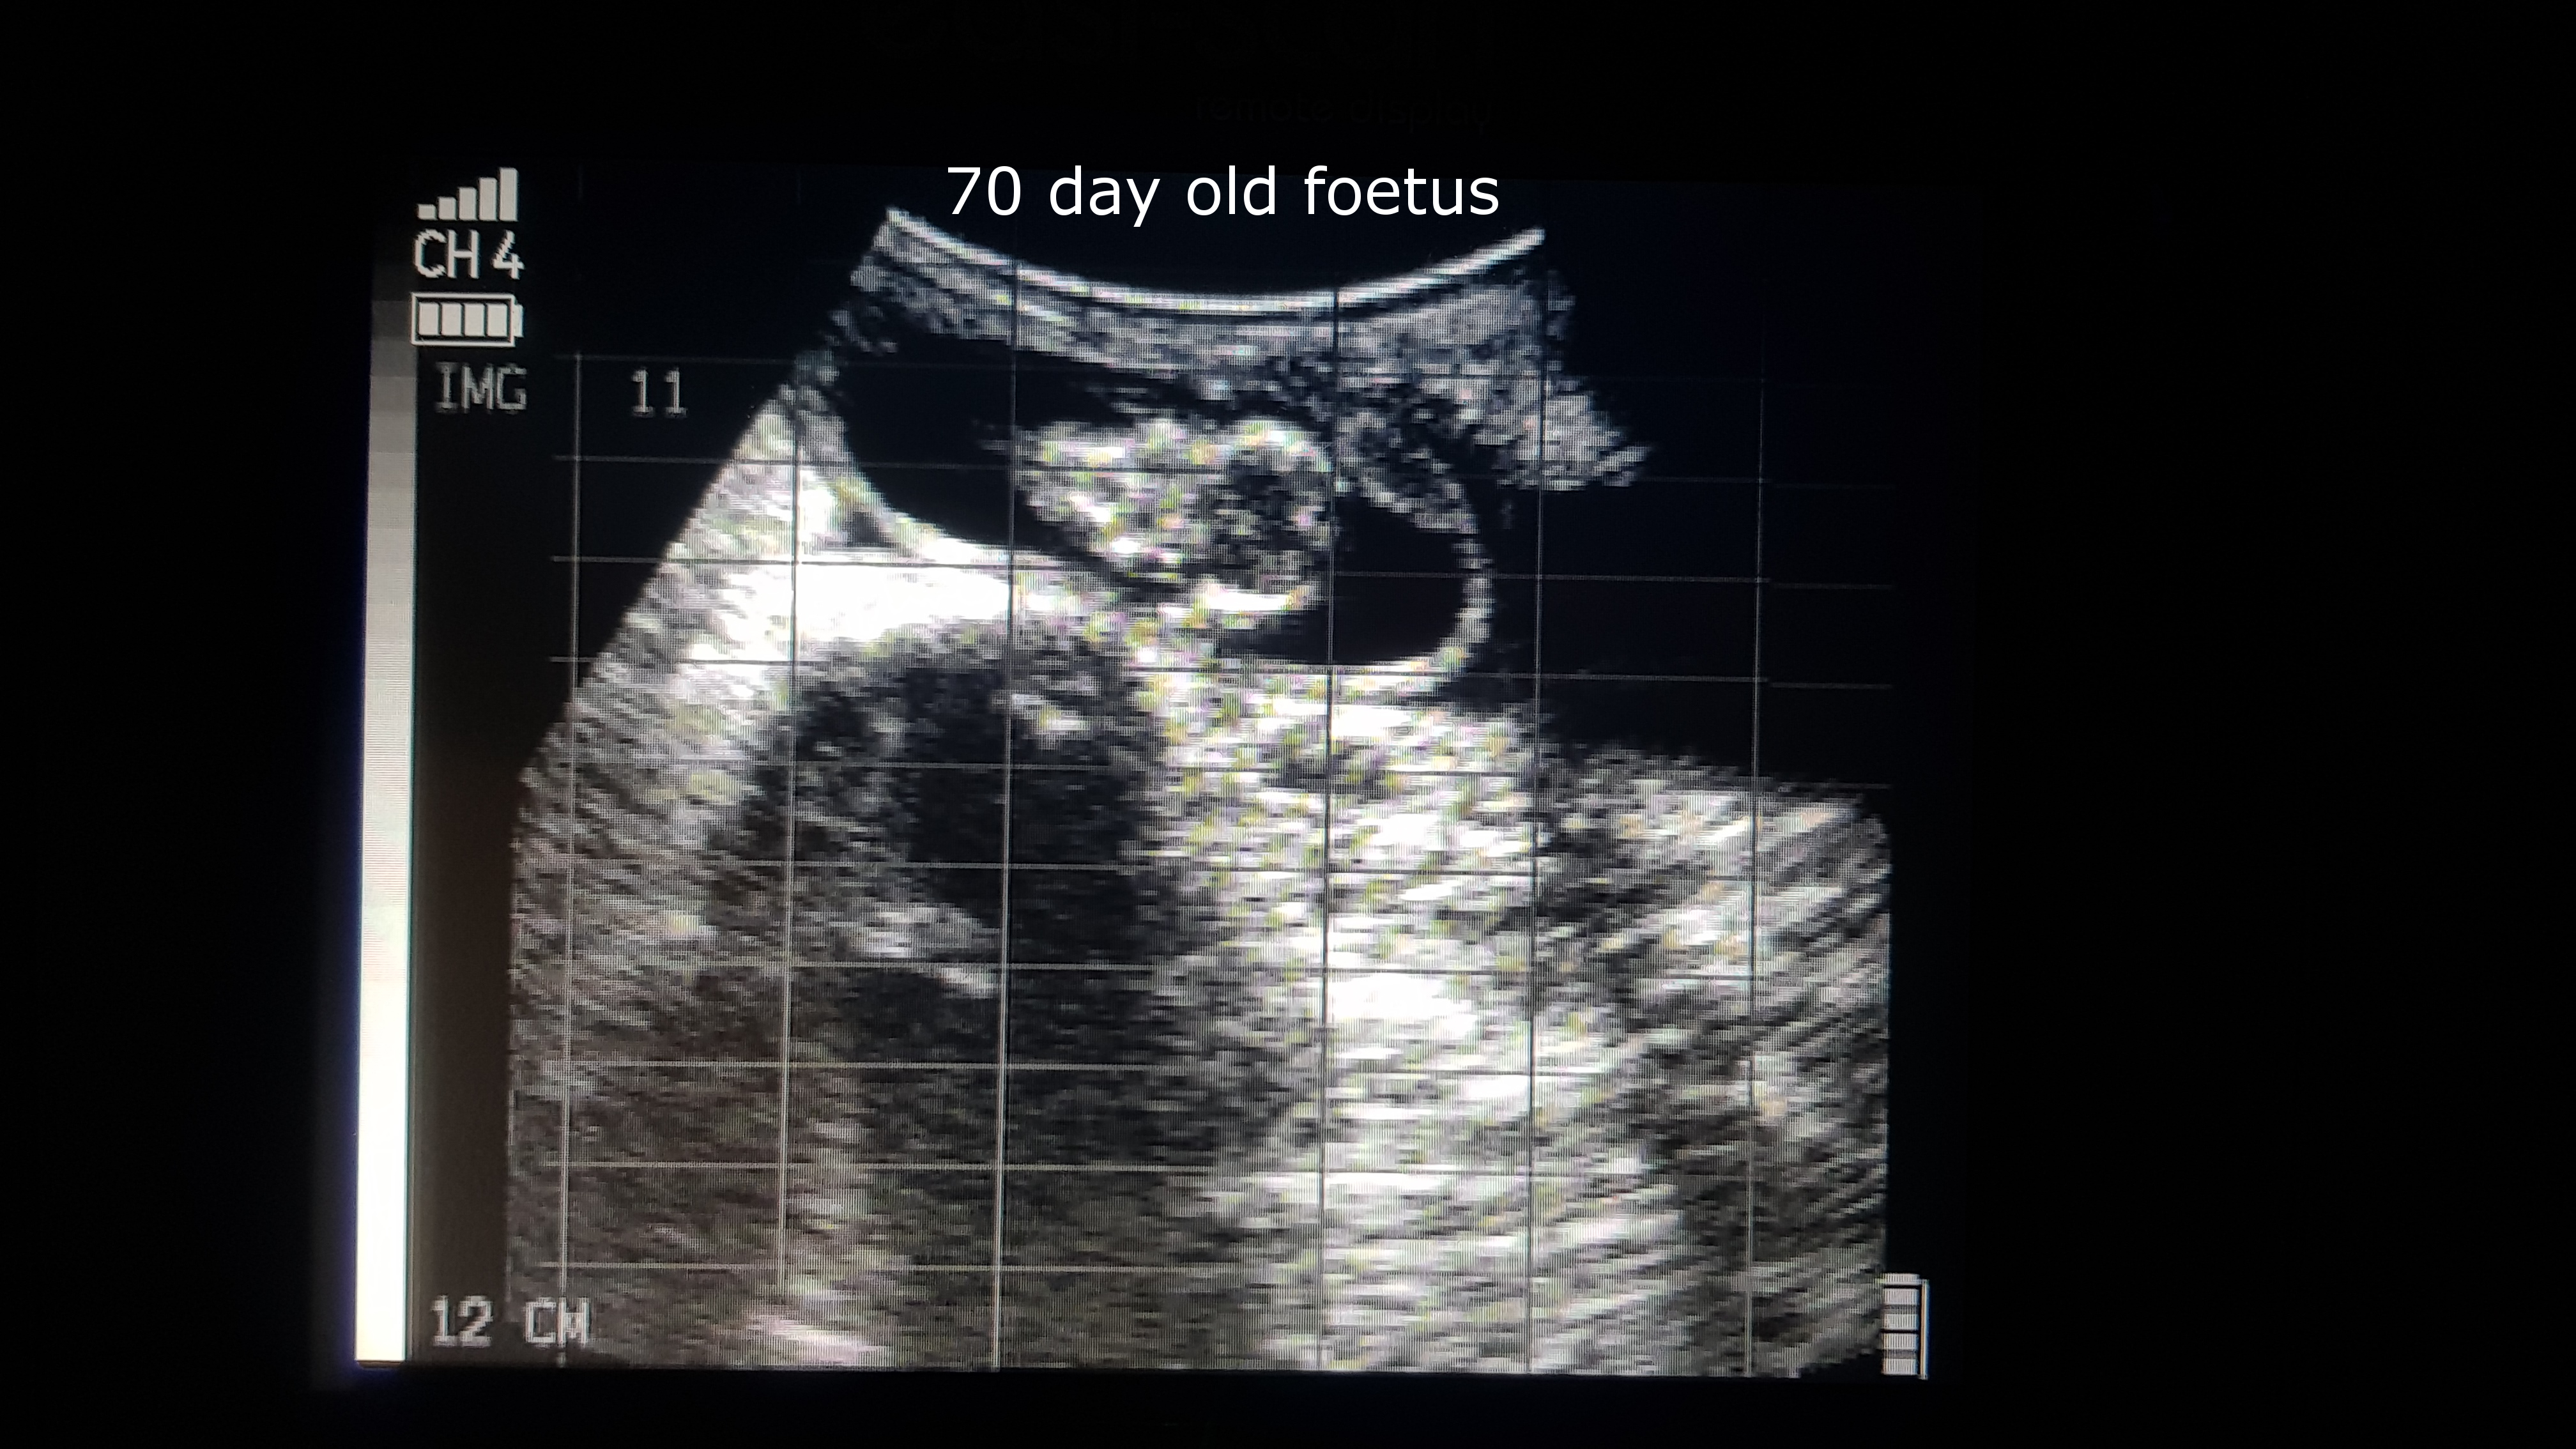

This more advanced service not only determines whether each individual cow is in calf or not, but also provides an estimate of how old the calf is. Foetal aging is most accurately carried out between 40 and 100 days of gestation. Once the pregnancies advance, there is too much variation in foetal size to be accurate and often the foetus is sitting too low to be measured correctly. Therefore, it is important to plan ahead and scan early. Foetal aging in beef cattle has many advantages, including:

Click to enlarge images. These are examples of how first trimester pregnancies can be aged, either by measuring the head width or body length of the foetus.